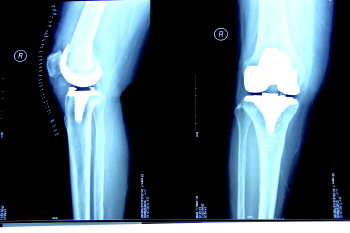

术后X光图

业务范围:骨外科设计的所有疾病,如各种骨及关节创伤及疾病、各种脊柱创伤及疾病,四肢创伤、断指(肢)再植、骨肿瘤等。尤其擅长骨关节内及近关节部位的骨折、脱位等复杂难治性骨折,骨性关节炎等退行性关节疾患的关节清理手术及各种人工关节置换手术,在骨折、关节镜、关节置换、股骨头坏死的早期治疗及显微外科方面处于本地区先进水平。

技术特色:科内拥有国内先进的移动式“C”形臂X光机,移动式骨科手术显微镜,美国“施乐辉”关节镜,大大提高了骨科手术成功率。临床和科研综合能力在本地区处于领先行列,如关节镜下肩袖损伤、肩胛盂唇损伤等关节疾患修复术、膝关节交叉韧带重建、关节镜下半月板全内缝合等。并率先在本地区开展了股骨头早期坏死髓芯减压钽棒植入术,已开展了肩袖损伤的开放手术及关节镜微创治疗取得了良好疗效。目前已完成全髋关节、膝关节置换及翻修术数百例,并开展了踝关节置换,取得了良好效果。